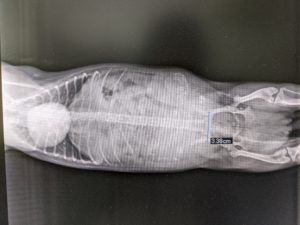

ジュジュちゃん(12月20日夜撮影)

ジュジュちゃん、日に日に破裂しそうなお腹です。( •̀ㅁ•́;)5.6頭は居ますね!!

こんなに大きいと、心配です。でも胎児に栄養が、行き渡るように沢山食べさせないといけません。出産予定15日前になりましたジュジュちゃん。1月4日頃出産予定です。可愛いベビーちゃんの誕生ワクワクドキドキです。